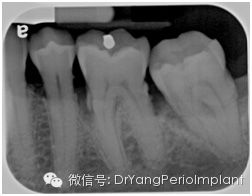

在讀根尖片前,首先要確定拍攝的X光片質量,換句話說,這張根尖片有沒有用於診斷的價值(diagnostic quality).

Prichard早在1972年就提出了判斷根尖片質量的標準(Prichard:Advanced periodontal disease: surgical and prostheticmanagement, 2版)

1. 顯示磨牙牙尖,無或略顯示HE(Occlusal table, 中文字典裏找不到這個字,唉!!)

2. 釉質,髓腔分明

3. 臨麵分開

4. 除非牙位異常,牙臨麵無重疊

達到診斷質量的根尖片(X光片取自筆者治療過的病人)。